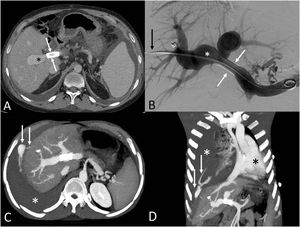

A 23-year-old liver transplant patient underwent a percutaneous transhepatic portal vein angioplasty (PTHPVA) as a procedure for correcting a clinically significant portal vein stenosis causing prehepatic portal hypertension (Fig. 1A and B). Right after the PTHPVA procedure, the patient developed shortness of breath and hypotension. An emergency CT showed active bleeding originating in the right hemidiaphragm surface (Fig. 1C–E). Because the patient was hemodynamically unstable, he was immediately transferred to the operating room, where a defect in the right hemidiaphragm was detected and closed. Percutaneous transhepatic portal vein angioplasty (PTHPVA) is a procedure performed in patients with clinically significant portal vein stenosis that involves direct right midaxillary puncture of the liver with the use of fluoroscopic and/or ultrasound guidance.1 Alternative techniques of portal vein angioplasty include a transsplenic and transjugular approaches, but these are less used.2 Hemothorax is an uncommon but well-known complication of PTHPVA; the rather large diameter of the dilators and catheters used in the procedure as well as the short puncture tract (making hemostasis difficult) have been claimed as risk factor for hemothorax. Low insertion of the right diaphragm and a high position of the liver graft are also potential factors that may cause hemothorax.1,2 This case reminds us that abdominal percutaneous interventional procedures can cause thoracic complications.

(A) Axial CT image obtained before the PTHPVA shows a portal vein stent (arrows) and a poststent portal vein dilatation (asterisk). (B) Digital subtraction angiogram shows the portal vein stent (arrows) and the poststent right portal vein dilatation (asterisk). (C) Axial maximum intensity projection (MIP) CT image performed after the PTHPVA procedure shows signs of an active bleeding (arrows) originating in the right hemidiaphragm. Note the presence of a right pleural effusion (asterisk). (D) Coronal MIP CT image shows signs of an active bleeding within the pleural space (arrows). Note the presence of a large right pleural effusion (white asterisk) causing a contralateral mediastinal shift (black asterisk).